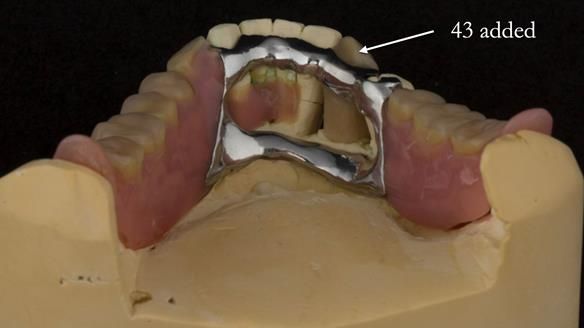

In 2022, tooth 43 fractured.

An artificial tooth was added to the RPD

by welding a cobalt–chrome tag to the bar

and adding the tooth.

The denture continued to function extremely well.